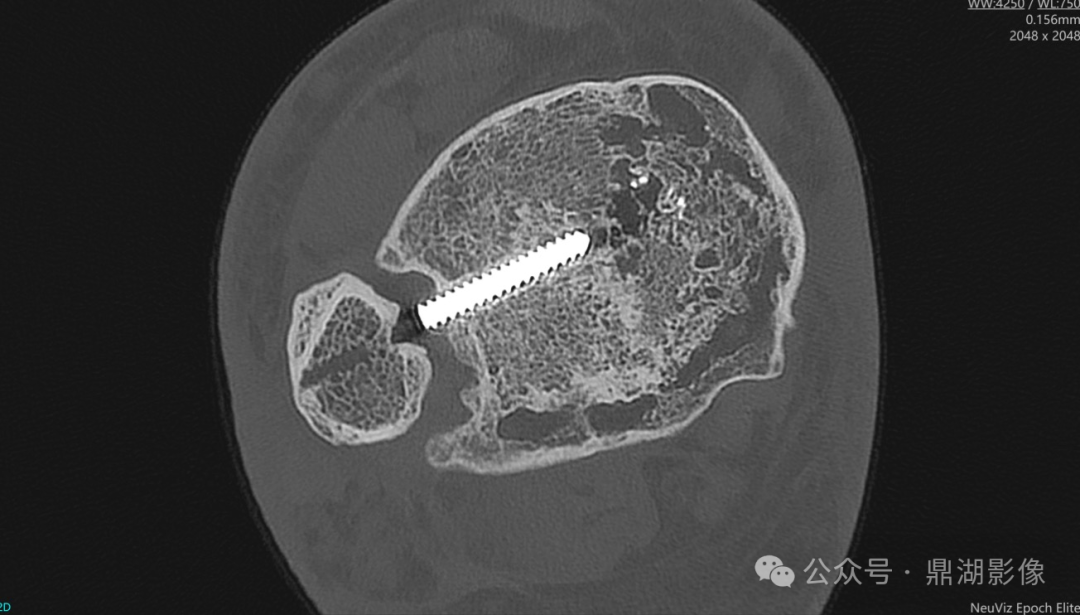

图 膝关节CT薄层扫描显示:金属内固定走行及结构,骨小梁及骨皮质等病变。

通过46.5lp/cm超高空间分辨率扫描结合多模态重建,可精准评估足踝螺钉内固定的解剖位置、骨整合状态及并发症,为临床决策提供关键依据。